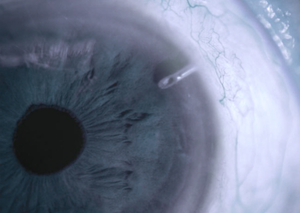

Лікування глаукоми у Львів Медікал Центрі починається з детальної діагностики, яка включає вимірювання внутрішньоочного тиску, огляд зорового нерва та оцінку стану сітківки. Після встановлення діагнозу лікар-офтальмолог обирає найбільш підходящий метод лікування, враховуючи індивідуальні особливості пацієнта.

Хірургічне втручання – проведення операції відповідно до обраного методу.